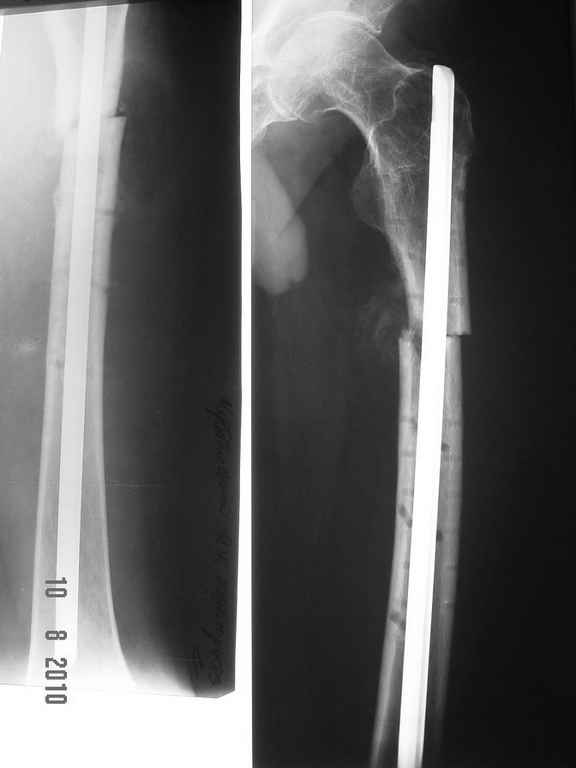

ДОбавил фото....

Условия больницы не блещут как собственно и финансовые возможности больного. Варианты типа БИОС, бусы с антибиотиками наверное так и останутся "вариантами". Пока интересует вопрос - остеомиелит? что делать?